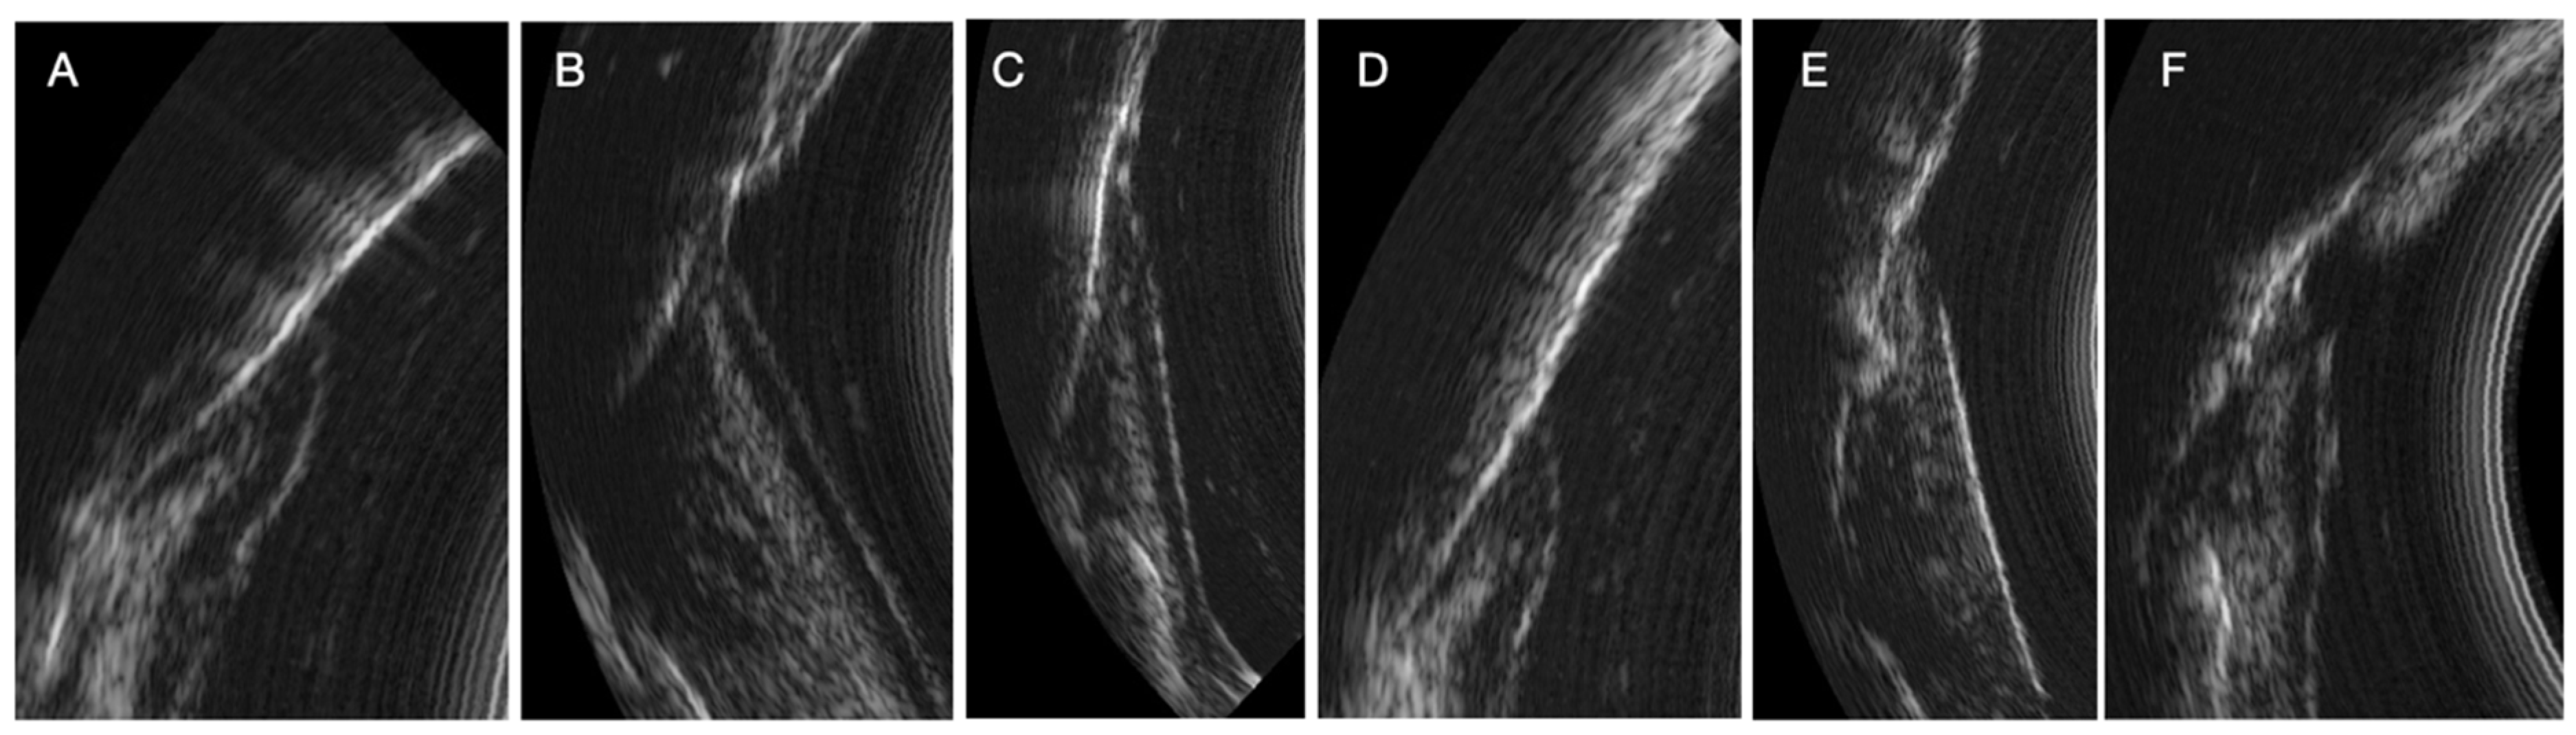

During the study, we observed many variations in ultrasound images depending on the clinical situation (inflammatory area, presence of visible calculus, edema, spontaneous bleeding, normal situation). Indeed, the images can reveal the presence of inflammation in the deep gingival tissues. Sub-gingival calculus can also be visible. The image quality is also different because of the variation in the ultrasound signal [13]. The same is true for subgingival calculus which can also be objectified on the ultrasound images. Although many of these elements appear in the image, AI currently struggles to differentiate pocket depths from surrounding structures in certain clinical contexts. These structures need to be identified and characterized for more precise training of the AI (Figure 4)

Figure 4. Variations in periodontal ultrasound images. (A) Reference image with normal structures. (B) Presence of deep inflammation with visible connective tissue junction. (C) Presence of deep inflammation without visible connective tissue junction. (D) Presence of supragingival calculus. (E) Presence of subgingival calculus. (F) Presence of calculus above and below the gingival surface and deep inflammation.